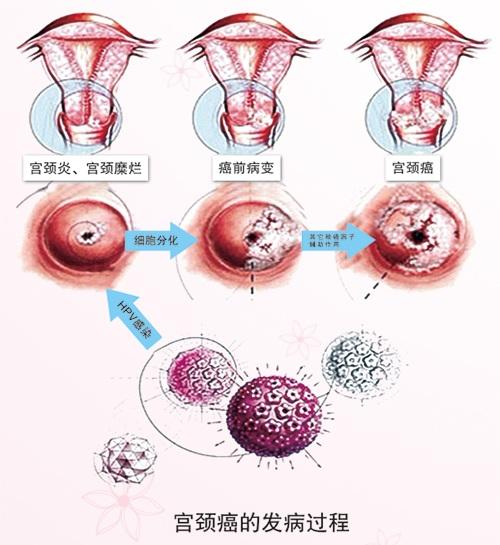

病例21-2017:一名患宫颈内癌的28岁孕妇 – NEJM医学前沿

身体出现这4个症状别忽视,可能是宫颈癌的前兆!